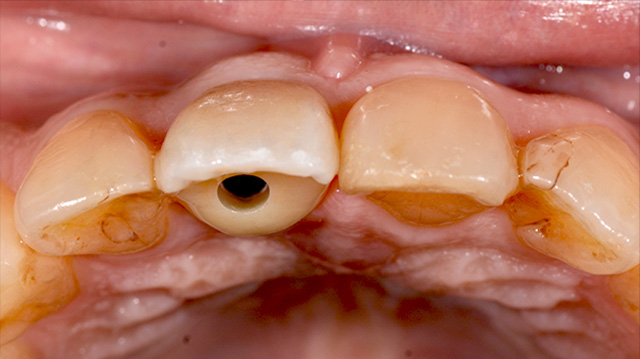

| 年代・性別 | 50代 男性 |

|---|---|

| 主訴 | インプラントをしたいが他の歯医者では難しいからと断られた |

| 治療期間 | 約1年 |

| 費用 |

仮歯 5,500円 ジルコニアクラウン 176,000円 インプラント 300,000円 インプラント仮歯 22,000円 サージカルガイド 70,000円 |